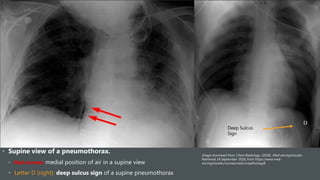

• Supine view of a pneumothorax.

• Red arrows: medial position of air in a supine view

• Letter D (right): deep sulcus sign of a supine pneumothorax

Deep Sulcus

Sign

• Supine viewof a pneumothorax. • Red arrows: medial position of air in a supine view • Letter D (right): deep sulcus sign of a supine pneumothorax Image borrowed from: Chest Radiology. (2018). Med-ed.virginia.edu. Retrieved 24 September 2018, from https://www.med- ed.virginia.edu/courses/rad/cxr/pathology8 Deep Sulcus Sign